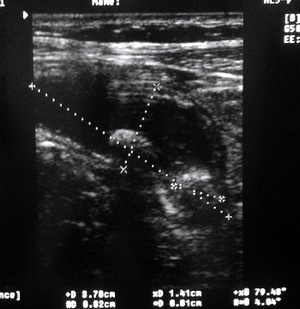

Как вы думаете, что это??? ;)

жидкостная тубулярная структура с конкрементами?

1. Воспаленный аппендикс, копролитами- фекалитами... :)

но скорее первое, чем второе..

Serg, вы правы. п1-совершенно верно!!! :D

О.аппендицит с картиной о.холецистита )